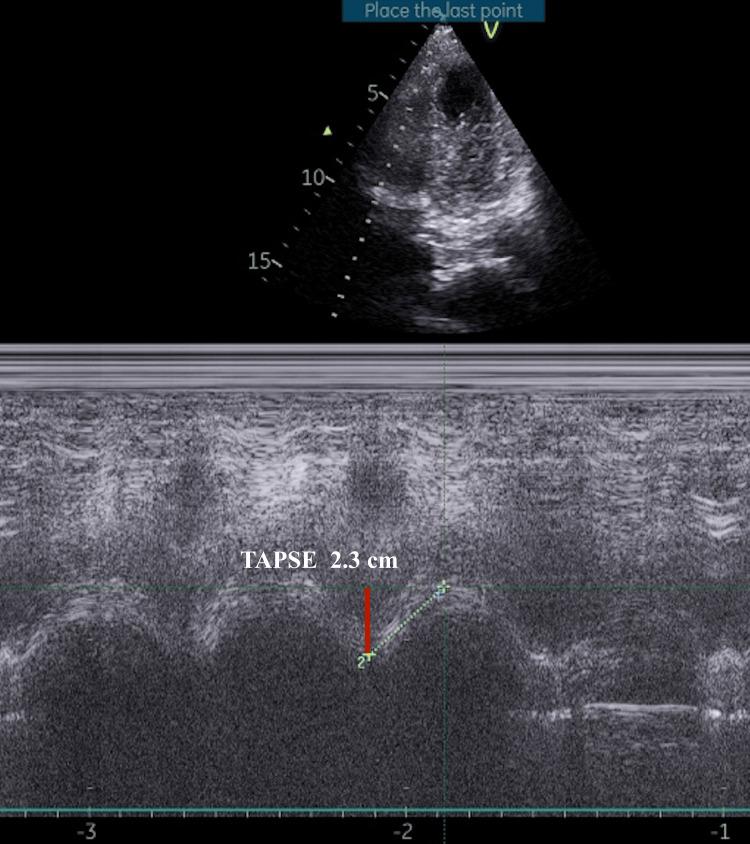

Central venous cannulation (CVC) is a routine procedure in critical care and surgical settings. Despite ultrasound guidance, complications like catheter coiling can occur. We report a case of CVC catheter coiling that led to waveform distortion and required corrective measures. A 23-year-old female patient underwent an emergency laparotomy for perforation peritonitis with underlying pulmonary tuberculosis. During the procedure, a triple-lumen CVC was placed in the left internal jugular vein (IJV) after an unsuccessful right IJV cannulation attempt. Upon placement, the CVP was significantly elevated at 31.2 mmHg with a distorted waveform showing exaggerated 'v wave' and diminished 'x descent'. A point-of-care echocardiogram excluded right heart abnormalities. Postoperatively, a chest X-ray revealed coiling of the CVC in the superior vena cava (SVC), forming a fishhook pattern. The catheter was partially withdrawn by 2 cm, resulting in a reduction in CVP to 12 mmHg and normalization of the waveform. The catheter was subsequently removed and replaced without complications. Catheter coiling is an uncommon but significant complication of CVC, even when performed under ultrasound guidance. It can lead to inaccurate CVP readings and waveform distortion, which may affect clinical decisions. Early recognition of abnormal waveforms and partial withdrawal of the catheter can correct the coiling and restore accurate hemodynamic monitoring. This case underscores the importance of waveform analysis as a diagnostic tool for detecting catheter malposition and mechanical complications.

中心静脉置管(CVC)是重症监护和手术环境中的常规操作。尽管有超声引导,但仍可能发生诸如导管盘绕等并发症。我们报告一例CVC导管盘绕病例,该病例导致波形失真并需要采取纠正措施。一名23岁女性患者因潜在肺结核并发穿孔性腹膜炎接受了急诊剖腹手术。手术过程中,在右颈内静脉(IJV)置管尝试失败后,在左颈内静脉置入了一根三腔CVC。置管后,中心静脉压(CVP)显著升高至31.2 mmHg,波形失真,出现夸张的“v波”且“x降支”减弱。床旁超声心动图排除了右心异常。术后,胸部X线显示CVC在上腔静脉(SVC)中盘绕,形成鱼钩样图案。将导管部分拔出2 cm,导致CVP降至12 mmHg且波形恢复正常。随后导管被取出并重新置入,未出现并发症。导管盘绕是CVC一种罕见但严重的并发症,即使在超声引导下进行操作时也会发生。它可导致CVP读数不准确和波形失真,这可能会影响临床决策。早期识别异常波形并部分拔出导管可纠正盘绕并恢复准确的血流动力学监测。该病例强调了波形分析作为检测导管位置异常和机械并发症的诊断工具的重要性。